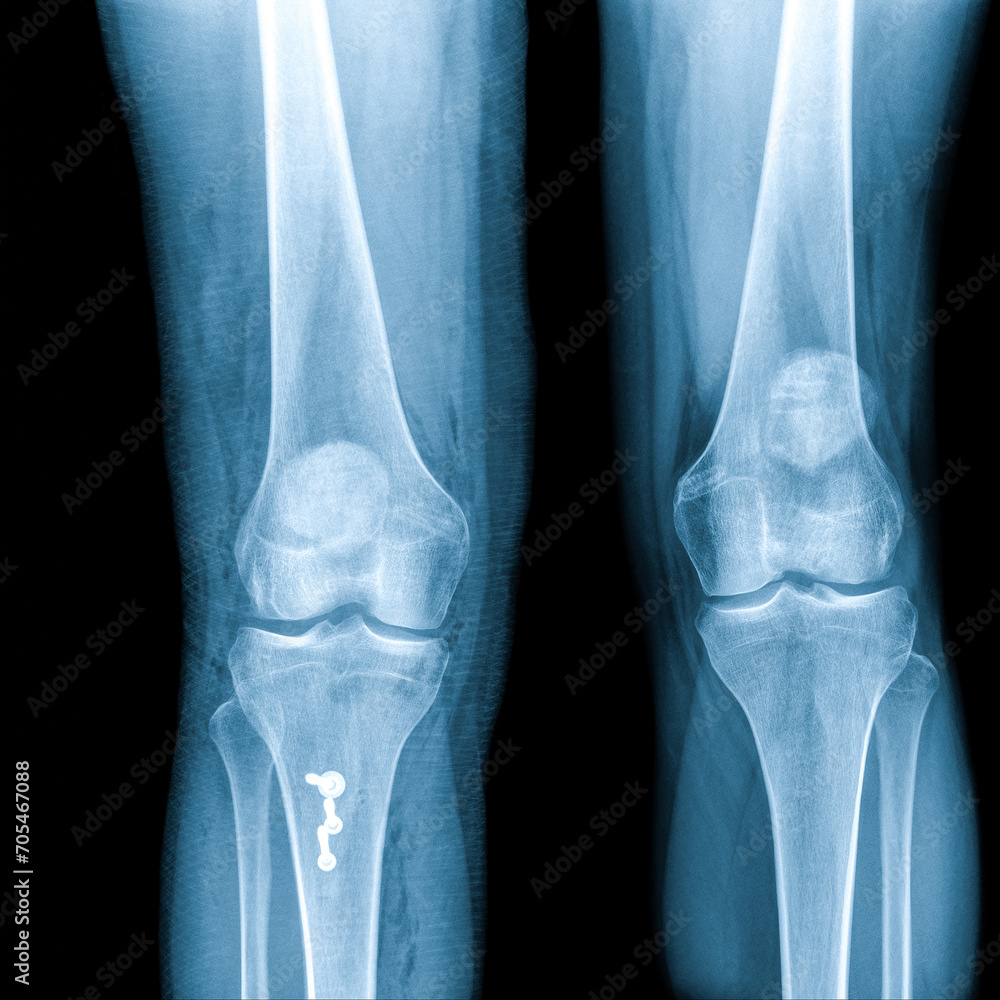

film xray both knee joint AP view for diagnosis knee pain from Knee Joint Fracture X Ray there are several ‘avulsion’ fractures that indicate significant joint derangement. this system divides tibial plateau fractures into six types: Horizontal ray (lateromedial) = supine + knee extended. Ct scans are used to further. Important examples are the segond fracture (avulsion from. increased signal intensity, thickening, and cysts within and adjacent to acl are common findings, and clinically. Knee Joint Fracture X Ray.

Film Xray Both Knee Joint AP View Name is Rosenberg View for Diagnosis Knee Joint Fracture X Ray increased signal intensity, thickening, and cysts within and adjacent to acl are common findings, and clinically insignificant (no. Important examples are the segond fracture (avulsion from. this system divides tibial plateau fractures into six types: Horizontal ray (lateromedial) = supine + knee extended. Ct scans are used to further. there are several ‘avulsion’ fractures that indicate significant. Knee Joint Fracture X Ray.

Premium Photo Xray knee (ap)views showing normal knee joint and Knee Joint Fracture X Ray increased signal intensity, thickening, and cysts within and adjacent to acl are common findings, and clinically insignificant (no. Ct scans are used to further. there are several ‘avulsion’ fractures that indicate significant joint derangement. Important examples are the segond fracture (avulsion from. Horizontal ray (lateromedial) = supine + knee extended. this system divides tibial plateau fractures into. Knee Joint Fracture X Ray.